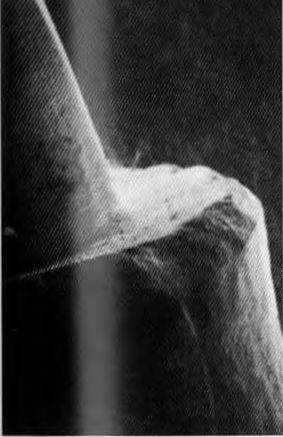

Рис. 3-17. СЭМ осевой стенки и границы культи зуба, препарированного под искусственную коронку I торпедовидным алмазным бором, а затем отполированного торпедовидным твердосплавным бором

дефекты в области границы препарирования (рис. 3-17, а, Ь). С помощью сканирующей электронной микроскопии (СЭМ) Scharer продемонстрировал, что для создания реставрации с хорошим краевым прилеганием обязательно наличие гладкой и четкой границы препарирования.